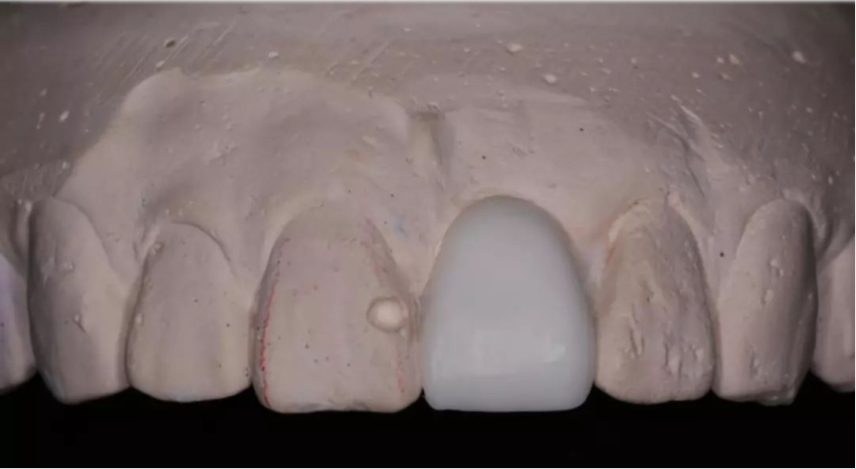

術(shù)前制取參考模型,排美學蠟型,實現(xiàn)以美學修復(fù)為導(dǎo)向的種植

使用U型管作為局部托盤,在石膏模型上,應(yīng)用聚醚硅橡膠進行印模

待硅橡膠凝固后,在印模中21缺牙區(qū)灌注阻射性材料(磷酸鋅或硫酸鋇/自凝牙托粉)

待阻射性材料凝固后,修整其邊緣及組織面

戴入患者口內(nèi),檢查U型管就位與石膏模型就位一致

檢查U型管及印模在口內(nèi)就位與石膏模型上一致